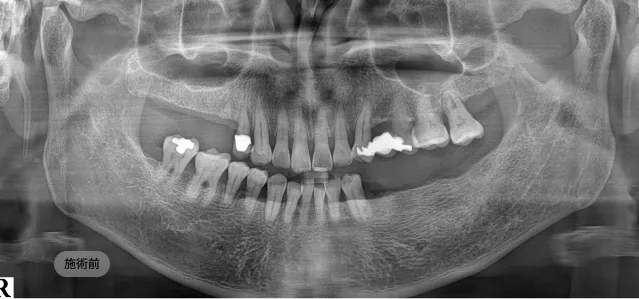

画面をドラッグして前/後を比較してみてください